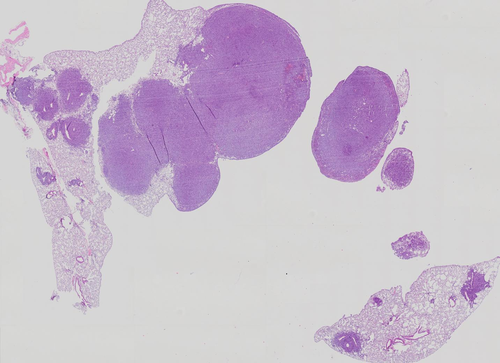

Le but de ce travail est de développer et évaluer des algorithmes d'analyse automatique d'images pour la quantification de grandes images biomédicales (comptages et caractérisation de cellules, descriptions de textures, mesures de surfaces, etc.). Les applications sont nombreuses, par exemple dans le contexte du cancer du poumon ou dans le cadre de recherches sur les mécanismes comme l'angiogénèse. Les algorithmes devront être intégrés au sein d'une plate-forme web existante (voir TFE 2009-2010 de A. Babilone et R. Rassaa) afin de pouvoir être utilisés facilement par des biologistes qui ont à analyser des centaines d'images de grandes tailles (> 30000 x 30000 pixels) dont des exemples sont présentés ci-dessous.